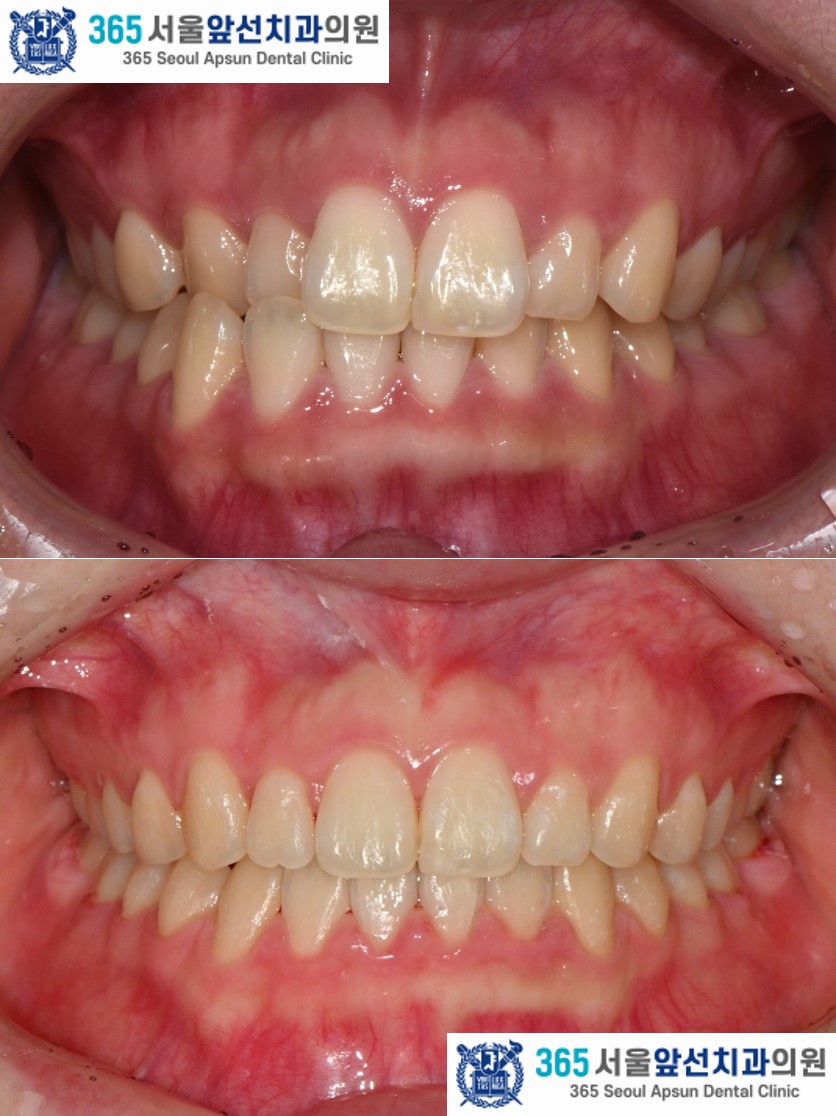

촬영일시 : 2024.10.23. 치료 전, 우측 측절치와 견치(송곳니)의 반대교합과 정중선 불일치가 관찰됩니다. 양측 상악 측절치가 5.6mm 폭경으로 왜소치 경향을 보이며 Bolton 의 전치부 비율이 86.73으로, 이상적인 윗니와 아랫니 앞니의 비율을 고려한 폭경에 비해 5.0mm가 부족합니다. 이 경우, 왜소치의 폭경을 키워 수복한다면 이상적인 교합을 형성할 수 있습니다. 해당 환자분께서는 왜소치의 수복 없이 치료하기를 원하셔서, 보상적으로 하악 치열의 폭경 감소와 Canine key compromise를 통해 최대한 심미적이고 기능적인 교합을 만들어드렸습니다.

촬영일시 : 2025.11.12. 치료 후의 모습입니다. 2024년 11월 16일 치료를 개시하여 2025년 11월 12일에 교정치료를 종료하였으며 총 12개월의 치료기간이 소요되었습니다. 치열이 가지런하게 배열되었고 목표하였던 반대교합의 해소, 정중선 불일치 개선이 완료되었습니다. 왜소치 수복 없이 구치부 1급 관계와 견치 유도 및 전치 유도가 가능한 교합이 잘 만들어졌습니다. 더불어 입술의 비틀어짐도 자연스럽게 해소되셨습니다. ![]() 촬영일시 : 2024.10.23. / 2025.11.12. 앞니의 반대교합이 있으셨던 환자분의 12개월 간의 치료 증례를 소개해드렸습니다. 환자분께서 정기적인 내원에 적극 협조해주셔서 치료기간이 단축되었던 것 같습니다.^^ 반대교합, 정중선 불일치, 비뚤한 치열이 고민이신 환자분들께서는 내원하셔서 교정 진단 받아보시길 바랍니다. 감사합니다.